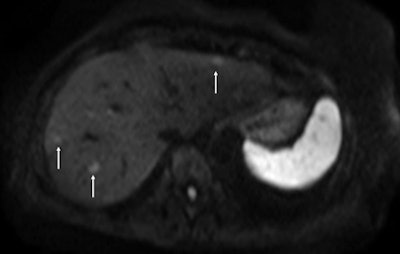

"Four years ago, intraoperative ultrasound sometimes revealed new lesions that had been missed in scans for staging colorectal liver metastasis. Now with diffusion-weighted MRI and the use of hepato-specific MR contrast agents, this is very unlikely to happen," she said, pointing to further details about surgical indications and candidates' prognostic factors to be provided by Dr. Jacques Belghiti, head of the department of hepatobiliary surgery, at the same Paris hospital.

For pretreatment assessment, the focus of Vilgrain's presentation, it is essential to choose the correct treatment plan for the patient, and MRI plays a pivotal role in intrahepatic staging. CT is important for detecting extrahepatic involvement. If the metastatic liver is clearly resectable -- e.g., there are only a few lesions located in a limited, superficial area or confined to one liver lobe and the major vessels are not involved -- then the usual course is neoadjuvant chemotherapy followed by surgery. Imaging is still fundamental for monitoring neoadjuvant chemotherapy response, as surgery performed after no response has a poor prognosis, while even partial response to such therapy improves the prognosis for the resectable patient, she explained. If findings show a borderline case, imaging is still crucial for guiding treatment decisions and monitoring tumor response to chemotherapy.